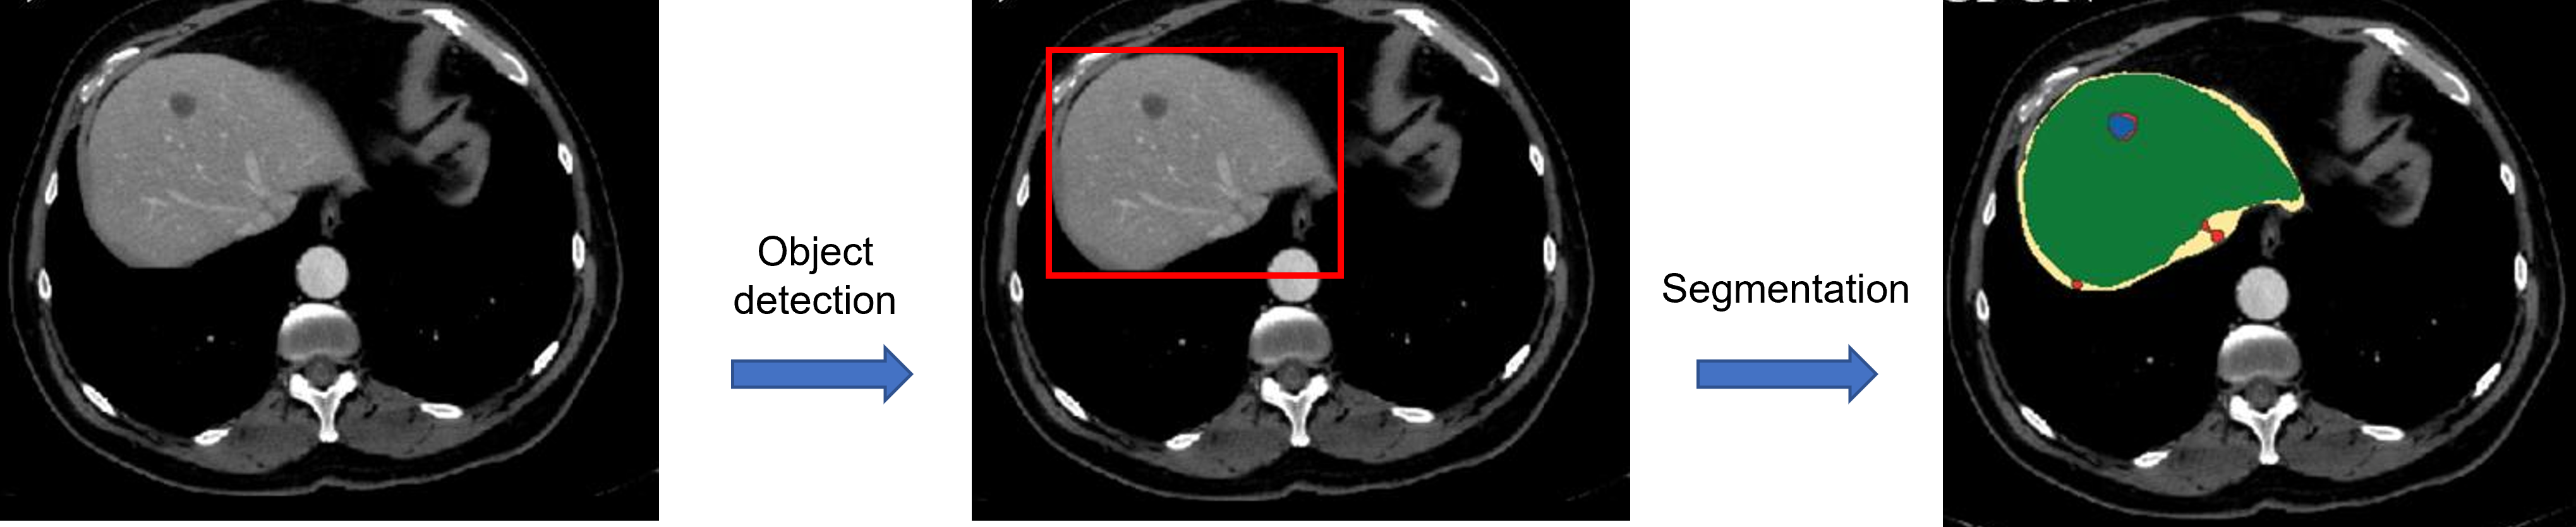

CNN, Object detection, Segmentation 모두 각각의 task에 대한 성능을 평가하기 위한 지표들이 존재합니다. (ex: F1 score, ACC, mAP, Dice loss, etc ...) 예를 들어, CNN model에서는 VGGNet보다 ResNet의 ACC가 더 좋으면 ResNet이 더 좋은 모델이라고 (일반적으로) 평가하죠.